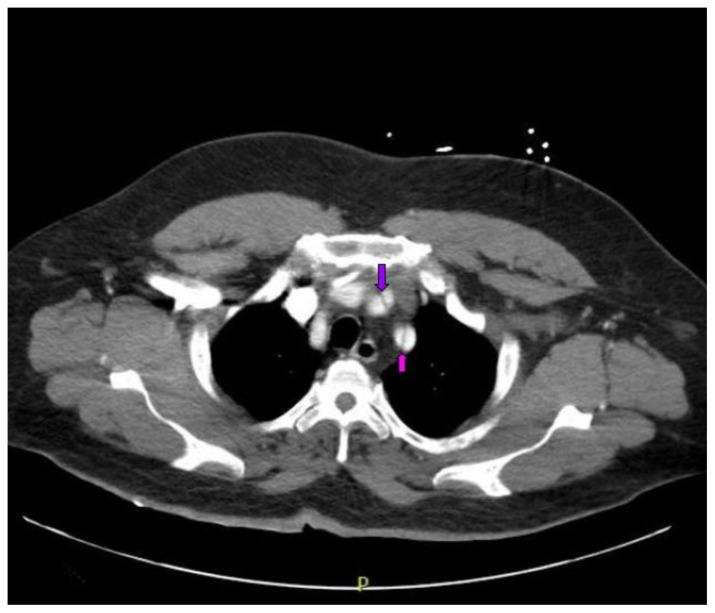

Acute aortic dissection is a life-threatening event caused by separation of the aortic layers that requires prompt management and surgical consultation. We present the case of a 53-year-old male who developed acute, severe chest pain radiating to his back at a community hospital and was transferred to a tertiary center for definitive surgical management. The patient's aortic dissection was diagnosed via computed tomography angiography. He was started on rate-control and blood pressure medications, and was admitted emergently to the operating room. Emergency physicians should obtain immediate surgical consultation, promptly start medications for rate and blood pressure control, and administer analgesia in order to stabilize their patient and decrease the shear forces that would further propagate an aortic dissection.

急性主动脉夹层是一种由主动脉各层分离引起的危及生命的事件,需要及时处理并进行外科会诊。我们报告一例53岁男性病例,该患者在社区医院出现急性、严重的胸痛并放射至背部,随后被转至三级中心进行确定性手术治疗。患者的主动脉夹层通过计算机断层扫描血管造影术确诊。他开始接受心率控制和血压药物治疗,并紧急送入手术室。急诊医生应立即进行外科会诊,迅速开始使用控制心率和血压的药物,并给予镇痛治疗,以稳定患者病情并降低会进一步加重主动脉夹层的剪切力。